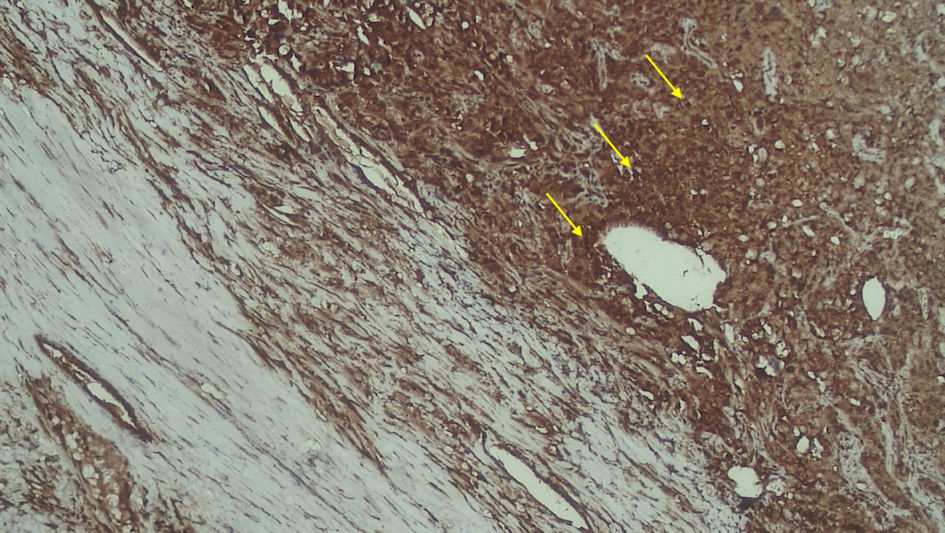

Subjects involved in this research were similar in age. However, most of the subjects involved in this study were male (Table 1). FAP expression correlated positively with TACS despite the tumor being in the stromal or intratumoral (y = 4.5x - 0.6667 in intratumoral tumors, and y = 4.5x - 1.6667 in stromal tumors, as seen in Figure 1). According to the Spearman rho test results, there was a positive correlation between the TACS degree to intratumor samples (96%) and stromal samples (84%), respectively accounted for 25 and 22 patients (y = 0.5x + 0.8; P = 0.0001) (Fig. 2). Histopathological images of TAC-3 collagen deposits (Fig. 3), and positive intratumoral and stromal FAP are illustrated below (Figs. 4, 5).

![]() Click for large image | Figure 5. Positive FAP expression in the stromal (yellow arrow). FAP: fibroblast activation protein. |

FAP is a marker of activated fibroblasts, which is found to be more abundant in tumors with invasive and aggressive phenotypes than those in noninvasive and nonaggressive types. Studies have suggested that FAP expression is associated with poorer prognosis. The effect of malignancy in mCCRCC can be detected by using TACS grading, which can be assessed by the changes in collagen structure; thus, these changes could be used as a prediction for the invasiveness of mCCRCC [8].

Based on our findings, we try to describe the FAP expression prevalence rate both in the stroma and intratumor of mCCRCC patients. Other studies have shown that FAP presence in mCCRCC patients is correlated with high stage, higher grade, and necrotic tumors with 10-years survival. Furthermore, the majority of the intratumor and stromal samples were found to have positive FAP expression, implying a poorer prognosis among a majority of the patients in our center and a prevalence of FAP. This finding is in line with another study that found that immunostaining FAP is 100% found in patients with sarcomatoid RCC [14].

Based on the previous study, the Fuhrman grading system had a moderate interobserver agreement if the four-grade Fuhrman scheme was applied [17]. Based on the paper written by Stanzione et al in 2020, it was stated that for the differentiation between high- and low-grade tumors, this method achieved an accuracy greater than 90% [18]. Therefore, it can be used to interpret the histopathological data in this study. Our present work suggests that TACS grading within the intratumoral is 15% and 32%, respectively, for TACS-1 and TACS-2; 50% in TACS-3. Meanwhile, the stromal TACS grading is 11% in TACS-1, 26 % in TACS-2, and 46% in TACS-3. It is found that FAP expression is correlated with TACS grading (r = 0.51, P = 0.001). Via the FAP, findings both in intratumor and stromal lesions can be used as markers for possible metastasis to other organs. A high TACS grading indicates perpendicular collagen formation, which will inform the occurrence of metastasis.